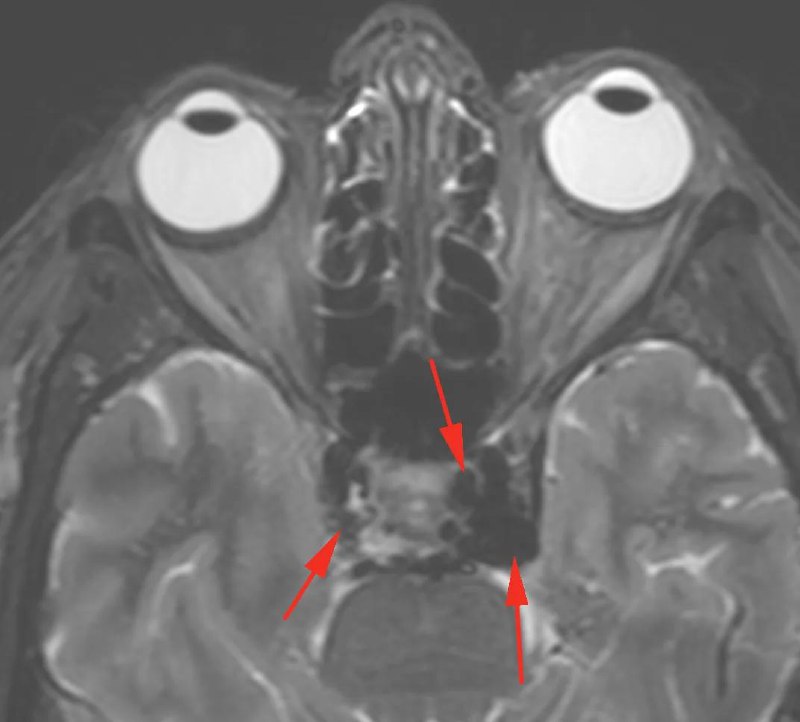

Женщина 73 года, головная боль, головокружение, шум. Левый глаз слезится , боль, ниже зрение стало, со слов «глаз выходит из орбиты»

Есть выпадение сигнала из-за ускорения потока в кавернозных синусах, больше слева, отёк наружных мышц левого глаза и клетчатки левой орбиты, левосторонний экзофтальм: картина характерна для каротидно-кавернозного соустья слева, рекомендуется КТА или срапзу консультация рентген-хирурга с решением вопроса о выполнении прямой ангиографии